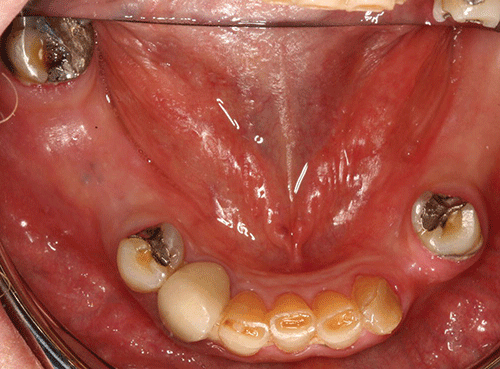

People with diabetes, whether type 1 or type 2, often experience dry mouth, or xerostomia. the problem is that it’s not just a sensation; it can have serious consequences at an oral level. xerostomia is associated with an increased risk of caries, infections, and periodontal disease. people who smoke, in people who have uncontrolled diabetes, people who have received treatment with bisphosphonates etc (more…) continue reading 1 2 3 4 popular posts 12 hour toothache remediesnatural cure wisdom teeth pain toothache remedies xerostomia toothache during pregnancy recent posts top 5 oral One of the most common symptoms of diabetes is dry mouth, or xerostomia. dry mouth is a common symptom in both type 1 and type 2 diabetes. not everyone with diabetes will experience it, though.

Dry mouth, also known as xerostomia, happens when you don't produce enough saliva. if this is something you're experiencing, we've got your back. let's look into why people with diabetes experience dry mouth, the oral implications of dry mouth, what you can do to support yourself, and ways to improve your oral hygiene. In addition to dry mouth symptoms, people with diabetesmellitus can also experience (in no particular order of significance): increased urination significant thirst fatigue blurred vision nausea slow healing of cuts and wounds. Dry mouth and diabetes one of the strongest indicators of diabetes is dry mouth, with a study showing that more than 90% of diabetic patients exhibit its symptoms. for individuals with type 1 and type 2 diabetes their elevated blood sugar levels and medications make them extremely susceptible to dry mouth.